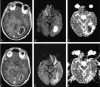

Fig 4.

Patient 2. Additional MR images. A–C, Follow-up image (A) obtained 15 days after surgical intervention shows reduced size of the abscess cavity. Corresponding DW image (B) shows hyperintensity in the abscess cavity with a decreased ADC to 0.76 × 10 −3mm 2/s (C), indicating reappearance of pus. Second drainage was performed 1 day later. D–F, Forty days after second intervention, follow-up images show resolution of the abscess cavity, with residual hypointensity on contrast-enhanced T1-weighted image and no abnormality on DW images.